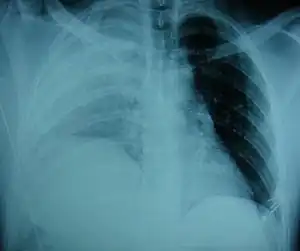

An X-ray showing a raised diaphragm on the right due to a rupture of the diaphragm on that side.[1]

Physical examinations are not accurate, as there is usually no specific physical sign that can be used to diagnose this condition.[6] Thoracoscopic and laparoscopic methods can be accurate.[15] Chest X-ray is known to be unreliable in diagnosing diaphragmatic rupture;[7] it has low sensitivity and specificity for the injury.[8] Often another injury such as pulmonary contusion masks the injury on the X-ray film.[9] Half the time, initial X-rays are normal; in most of those that are not, hemothorax or pneumothorax is present.[7] A nasogastric tube from the stomach may appear on the film in the chest cavity; this sign is pathognomonic for diaphragmatic rupture, but it is rare.[7] The X-ray is better able to detect the injury when taken from the back with the person upright, but this is not usually possible because the person is usually not stable enough; thus it is usually taken from the front with the person lying supine.[8] Positive pressure ventilation helps keep the abdominal organs from herniating into the chest cavity, but this also can prevent the injury from being discovered on an X-ray.[7]

Between 50 and 80% of diaphragmatic ruptures occur on the left side.[8] It is possible that the liver, which is situated in the right upper quadrant of the abdomen, cushions the diaphragm.[9] However, injuries occurring on the left side are also easier to detect in X-ray films.[7] Half of diaphragmatic ruptures that occur on the right side are associated with liver injury.[8] Injuries occurring on the right are associated with a higher rate of death and more numerous and serious accompanying injuries.[13] Bilateral diaphragmatic rupture, which occurs in 1–2% of ruptures, is associated with a much higher death rate (mortality) than injuries that occur on just one side.[8]